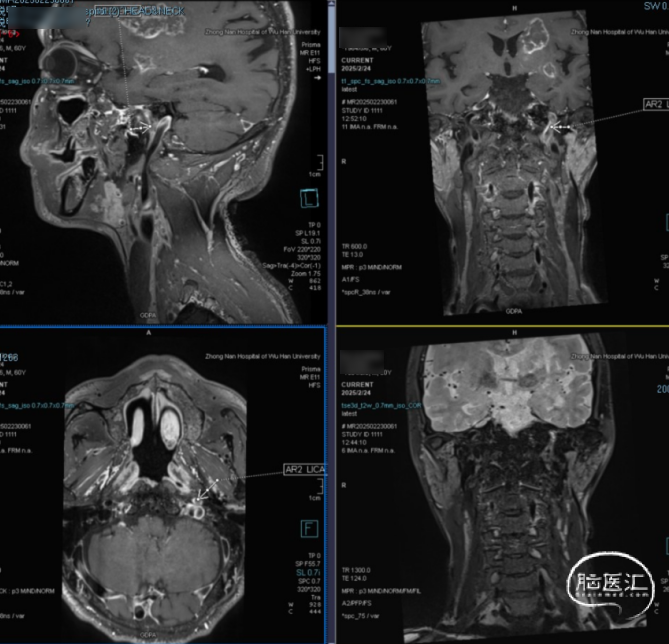

高分辨核磁:颈动脉斑块分析提示左侧颈内动脉全程管径缩窄,C1及C4-C5段不稳定斑块形成伴管腔闭塞。

本病例为60岁男性患者,因“右侧肢体乏力10天余”入院,术前影像提示左侧颈内动脉自起始段闭塞,右侧颈内动脉C4段重度狭窄,且左侧大脑中动脉供血区由前交通动脉及颈外动脉皮层支代偿供血。患者既往有糖尿病病史,血糖控制不详,存在动脉粥样硬化危险因素。病例特点为慢性闭塞合并近期症状加重,提示左侧颈内动脉闭塞为本次脑梗死的责任血管。难点在于: